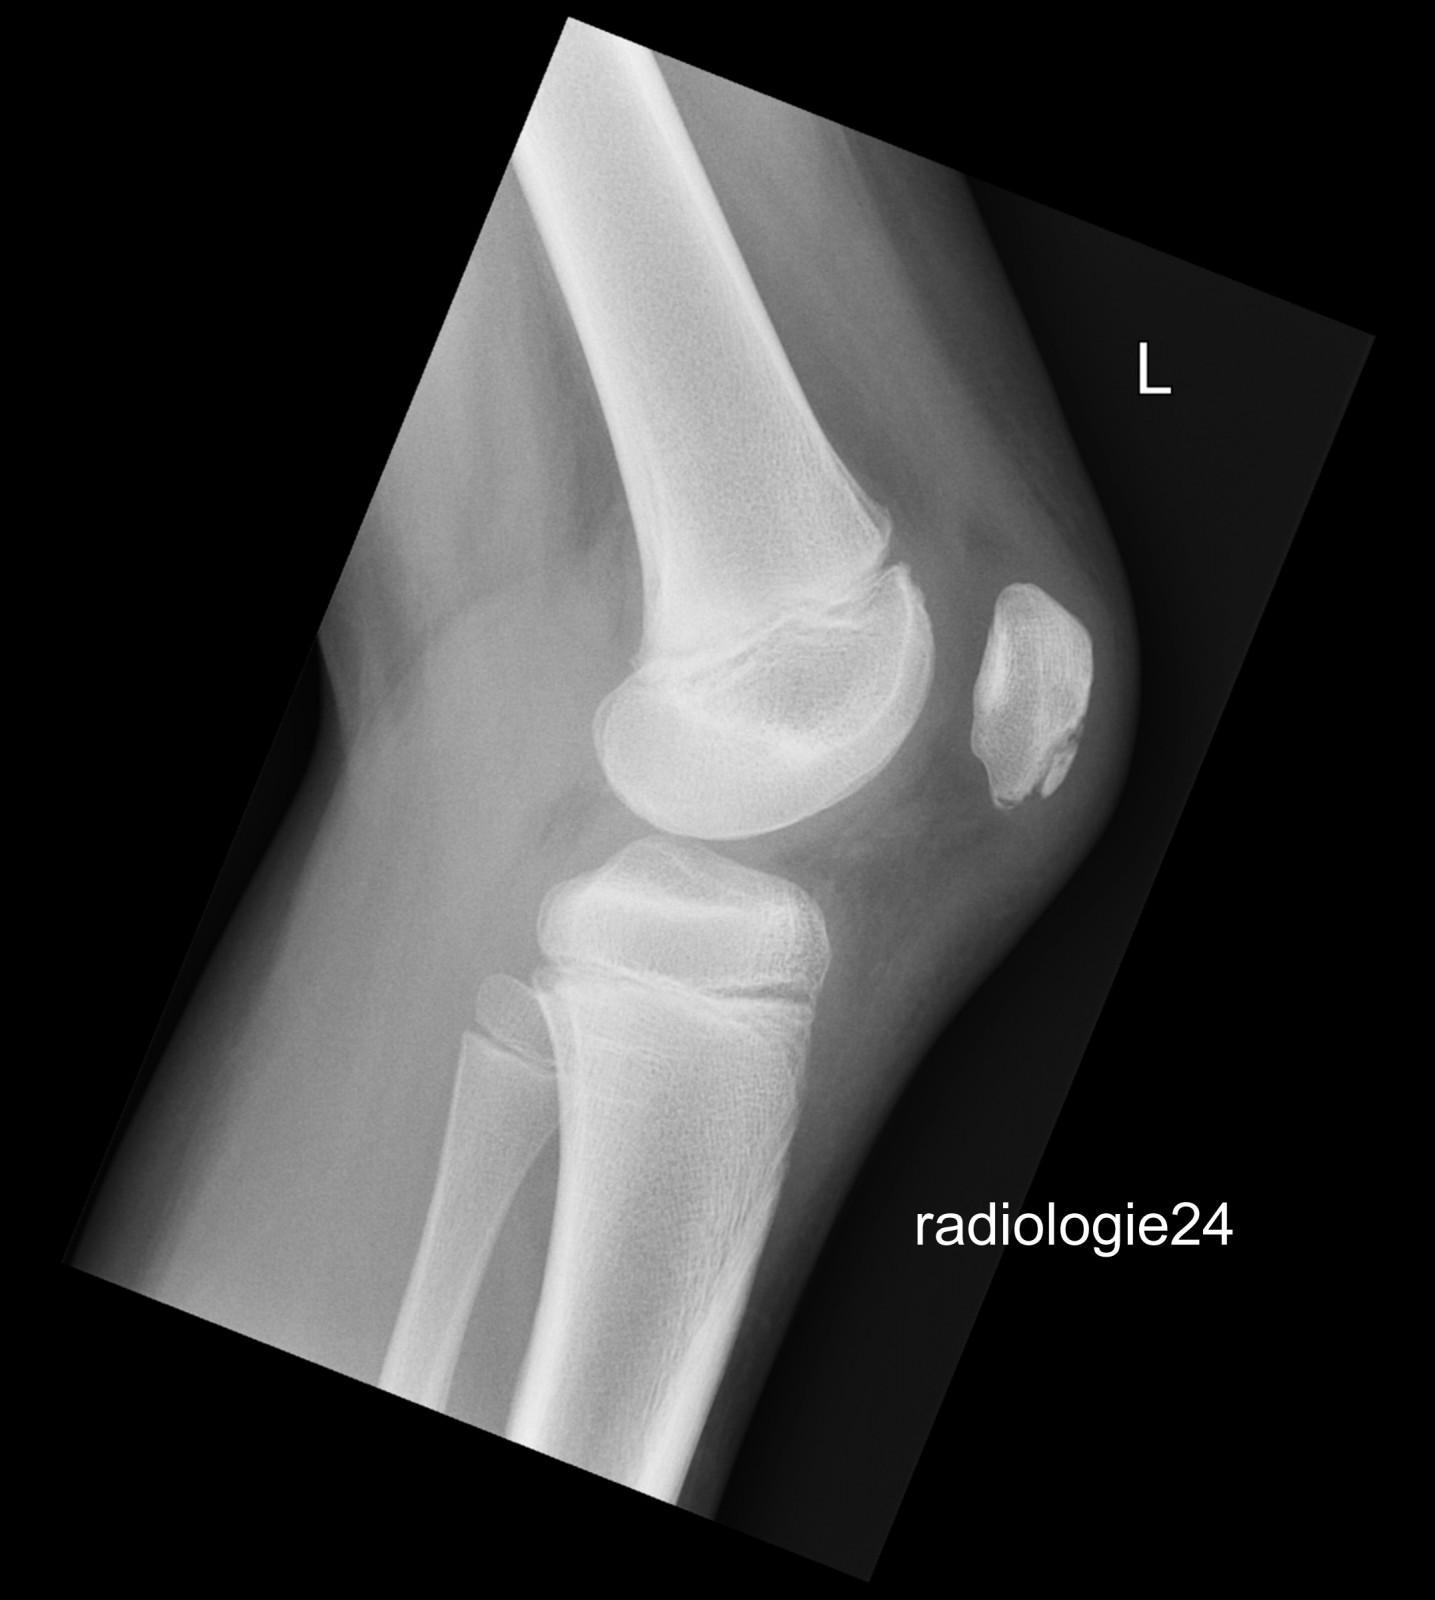

Röntgenfall des Monats